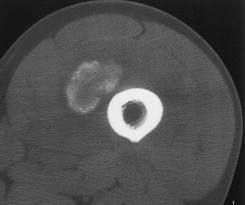

1. MIOSITIS OSIFICANTES

• Proceso calcificatorio del músculo. asociado a traumatismos y contusiones